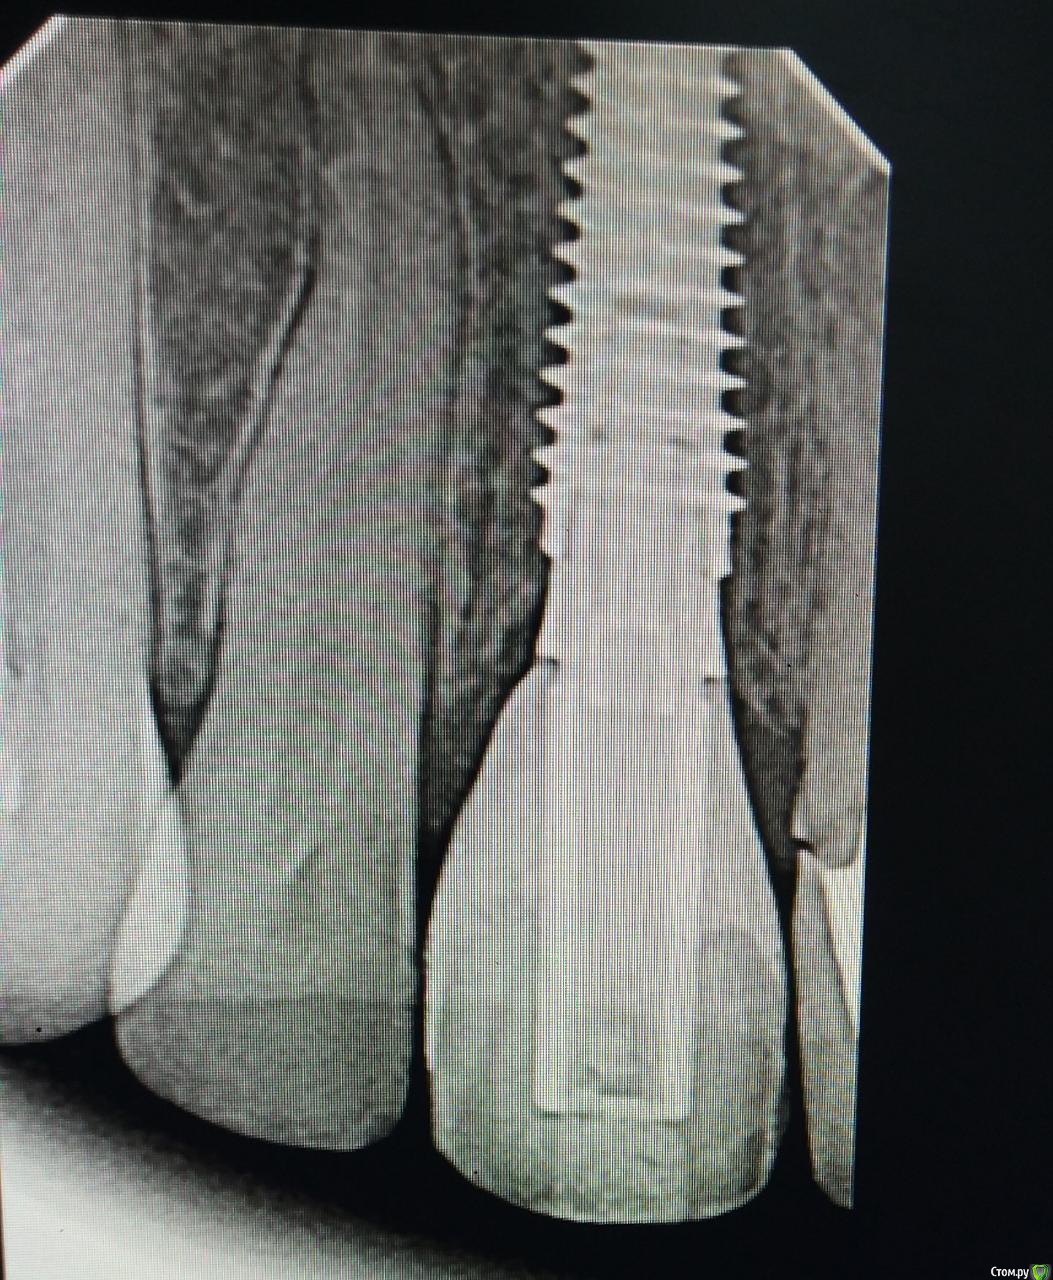

Irouil Опубликовано 2 мая, 2020 Поделиться Опубликовано 2 мая, 2020 Рентгенов дайте Ссылка на комментарий

Александр07 Опубликовано 2 мая, 2020 Автор Поделиться Опубликовано 2 мая, 2020 Рентгенов дайте Ссылка на комментарий

Дмитрий М Опубликовано 2 мая, 2020 Поделиться Опубликовано 2 мая, 2020 Рентгенов дайтна 21 коронку менять будете? Ссылка на комментарий

Irouil Опубликовано 2 мая, 2020 Поделиться Опубликовано 2 мая, 2020 Я тоже не вижу, что тут еще давить. У коронки плохой контур в пришеечной части, но ближе к платформе винта коронка должна быть тоньше с таким рентгеном, значит там поддержка тканей еще уменьшится. Судя по оклюзионному снимку в оро-вестибулярном направлении коронке не хватает объёма, зенит тоже апикальнее необходимого. Надо разобраться с соседней 1-кой, если замена там коронки - вариант, то можно рассмотреть апикализацию зенита на зубе на 1 мм в итоге. Но, имхо, без хирургии тут не выйдет ничего Ссылка на комментарий